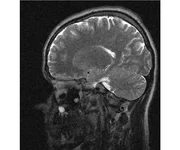

делал в обласной на siemense.В заключении выданом мне через 15мин.после мрт (легкая дегидрация)

Меня смутил факт выдачи заключения через 10мин(наверно они у них зарание напечатаные)я не медик.достаточно мимолётного взгляда на снимки?А вы видете на них гидроцефалию? Я лиш спросил куда идти с результатами томографии?и не хотел никого роздражать.

Я попросил взглянуть на снимки и сказать видна.ли на них гидроцефалия?или куда обратится за консультацией по этому вопросу?В мрт снимках наверно розбирается любой нервопатолог(я так предположил)

Я уже говорил, что независимо от того, есть на МРТ гидроцефалия или нет, лечиться тебе нужно только в том случае, если есть какие-либо проявления болезни, иначе на все эти анализы можешь забить... Но давай все-таки разберемся с томограммой.

Итак, с самого начала томограмма обозначала срез какого-либо органа на определенной глубине, позволяла заглянуть вовнутрь. При компьютерной томографии аппарат делает десятки срезов головного мозга в разных направлениях и из этого множества срезов он моделирует полноценное объемное изображение мозга в натуральную величину. Обрати внимание, компьютер работает не с этими миниатюрными изображениями, а с трехмерной моделью в масштабе 1:1. Эту модель вдоль и поперек анализирует суперсовременный компьютер, выполняющий миллионы операций в секунду. Только ***** может пытаться перепроверить компьютер, ведь человеку не хватит всей жизни чтобы проанализировать то, что компьютер с тобой сделал за 10 минут. Я хочу, чтобы ты это понял!

Ты разместл здесь несколько миниатюр и хочешь, чтобы врач по ним создал полноценное объемное изображение в натуральную величину, а потом осмотрел его со всех сторон и дал заключение? Но ведь это невозможно. Это просто насмешка над врачом, это издевательство над здравым смыслом. Принеси Букеру уменьшенный в 50 раз снимок зуба и спроси у него, в каком состоянии там корневые каналы. Или давай я дам тебе скрин со спутниковой карты города и попрошу тебя описать, какого цвета и какой модели запечатленная со спутника машина, какой у нее гос.номер, сколько в ней пассажиров, сколько из них мужчин и сколько женщин...

Надеюсь, ты понимаешь, что это невозможно. И воссоздать по приведенным тобой аватарам полную картину мозга тоже невозможно. Пойми, если уж называть вещи своими именами, то ты запостил полнейшую ***ню! Ты не хотел никого обидеть, ты ведь сам не ведал, что творил. Ты продемонстрировал полнейшую медицинскую безграмотность и полное невежество, но претензий к тебе нет. Ты ведь не один такой. Ты пожелал того, что сделать невозможно, и тут же у тебя нашлась сочувствующая, некая П., которую, по большому счету, надо бы послать в П., коль уж она считает, что врач должен тут сделать немедленно и бесплатно то, что делает немецкий компьютерный томограф ценой в миллионы долларов.